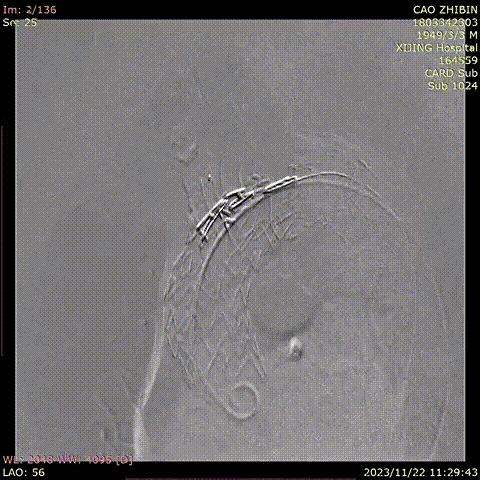

曹某,男,74岁,“胸背部疼痛10天”入院,主动脉CTA提示:主动脉弓可见多发穿透溃疡,较大之一径约1.2cm。高血压病史10年,血压最高190/80mmHg,糖尿病史12年。

术前CTA

术前

术后

手术用时80分钟